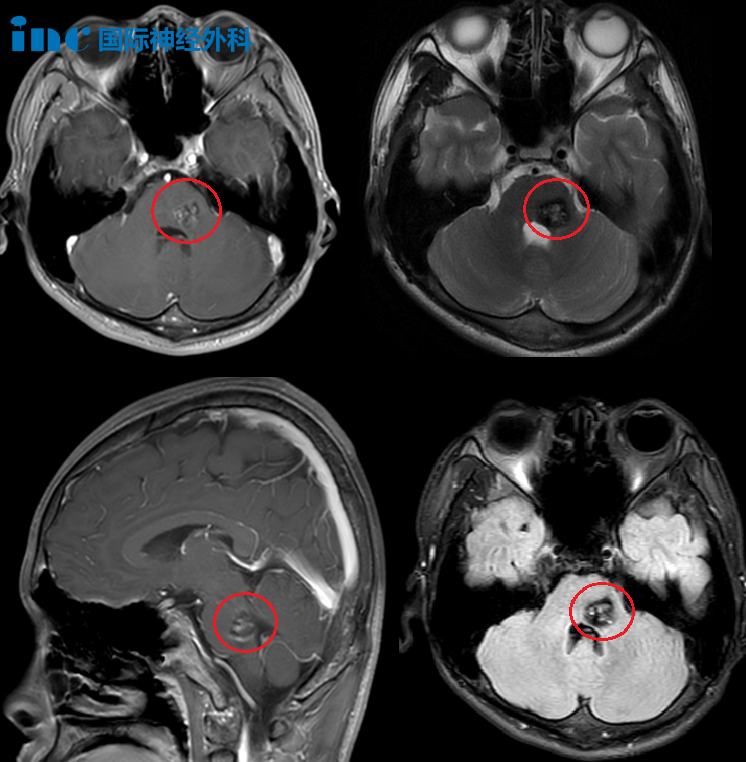

一向重视儿子健康的父母,心头警铃大作,火速送医。核磁共振的结果,如同晴天霹雳:脑干左侧海绵状血管瘤并出血!

这颗危险的“不定时炸弹”,就藏在控制生命核心的桥脑深处,体积大、位置险。“怎么治?” 小波父母跑遍多家医院,得到的建议却让他们坠入冰窟:

病灶位于桥脑左侧,并且与桥臂的交界处,病灶大,位置深。